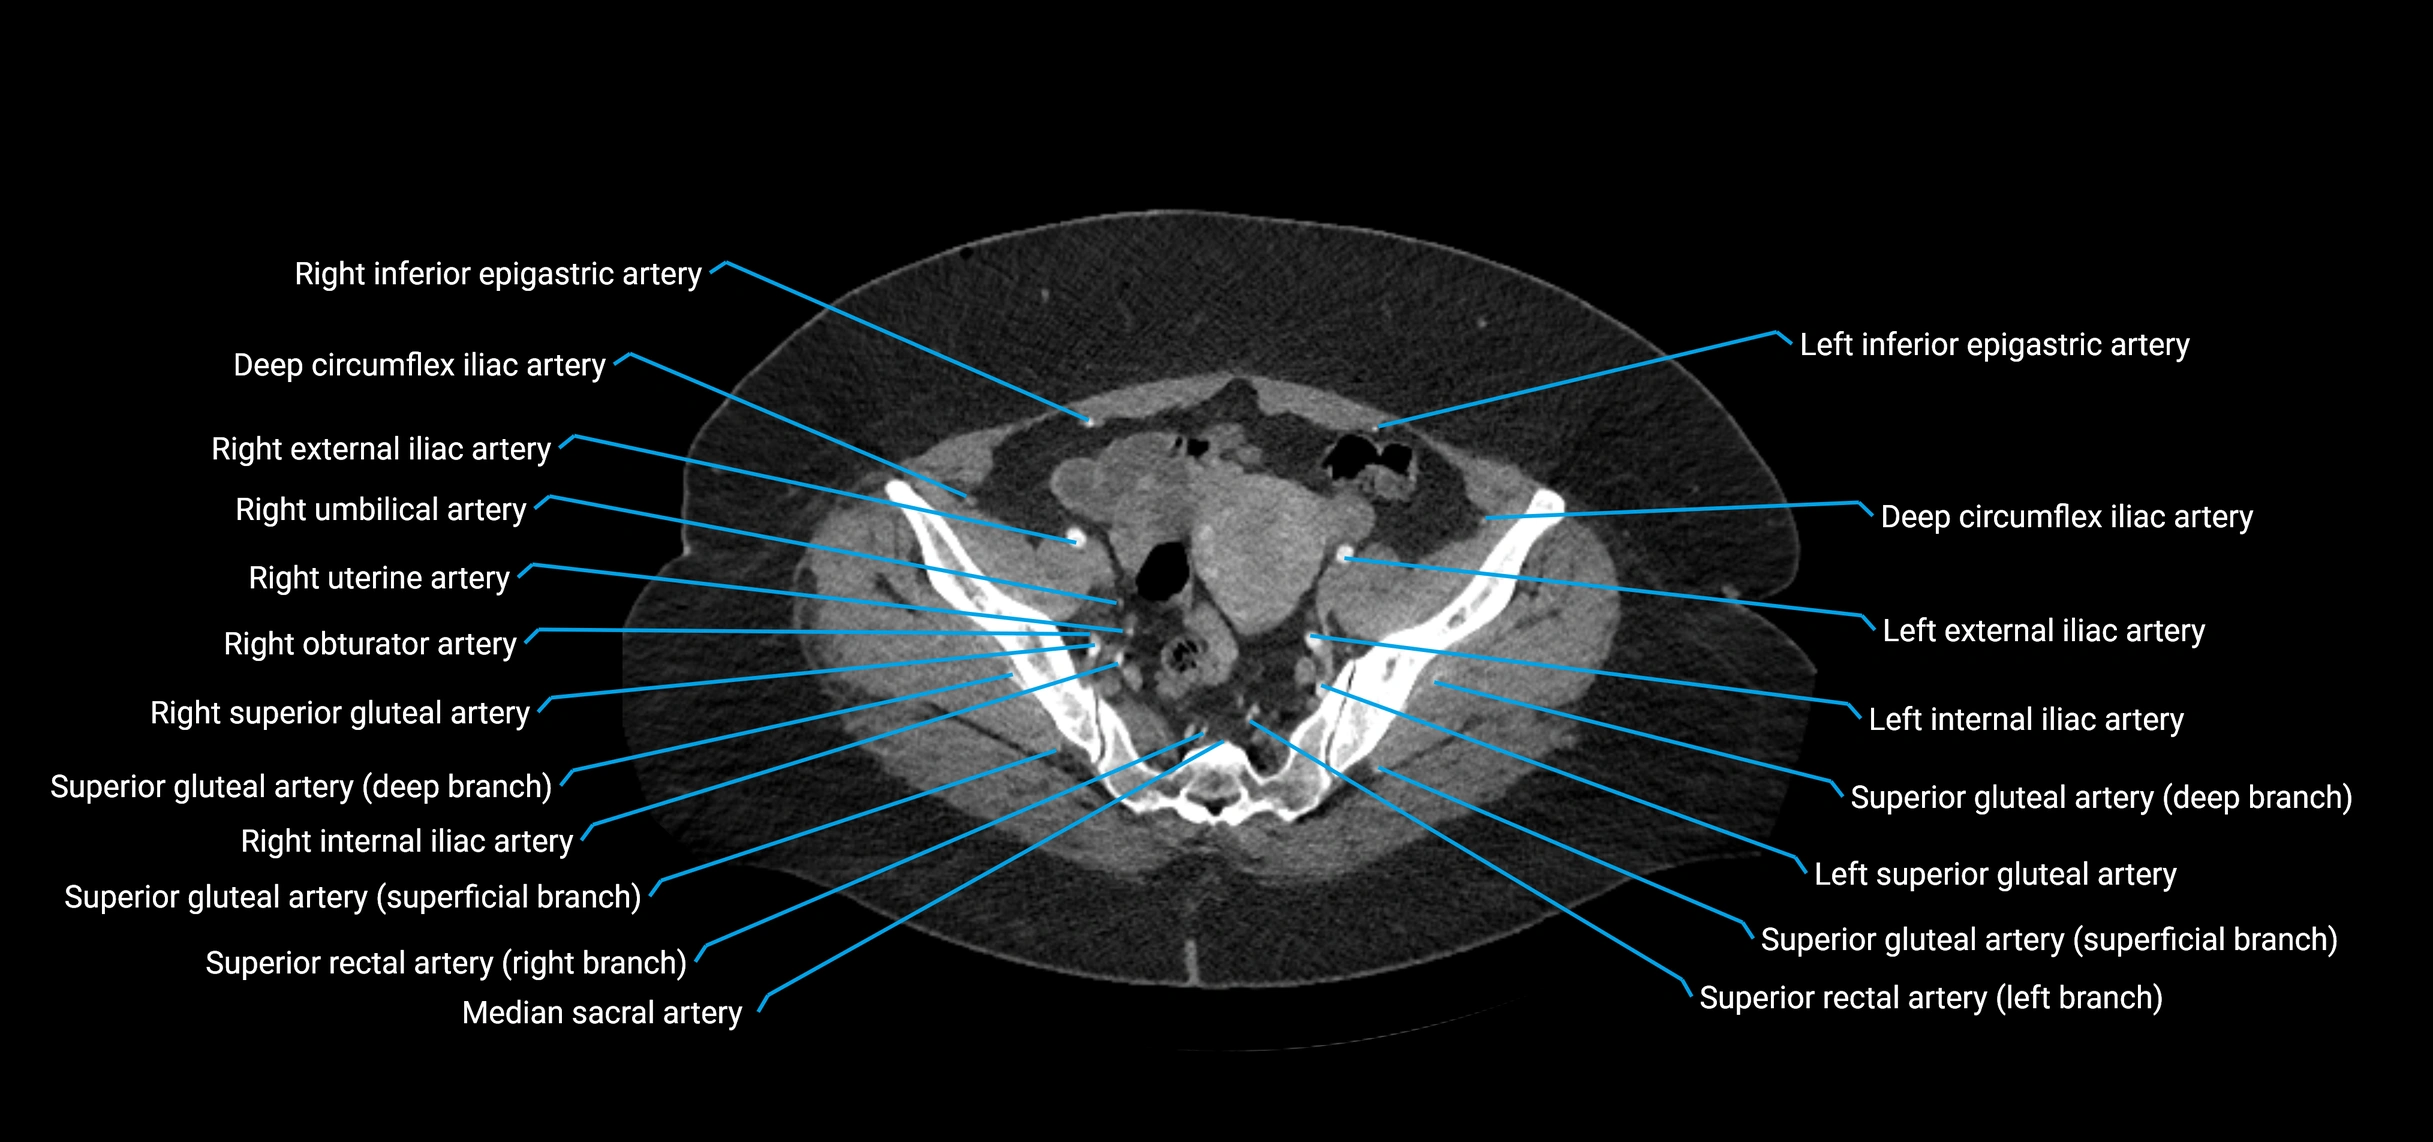

Contrast-enhanced CT (CTA):

• Gold standard for abdominal aortic imaging

• Provides excellent detail of lumen, wall, aneurysm, thrombus, and branch vessels

• Multiplanar and 3D reconstructions help in aneurysm measurement, stent graft planning, and dissection evaluation

• Detects acute rupture, traumatic injury, or occlusion with high sensitivity